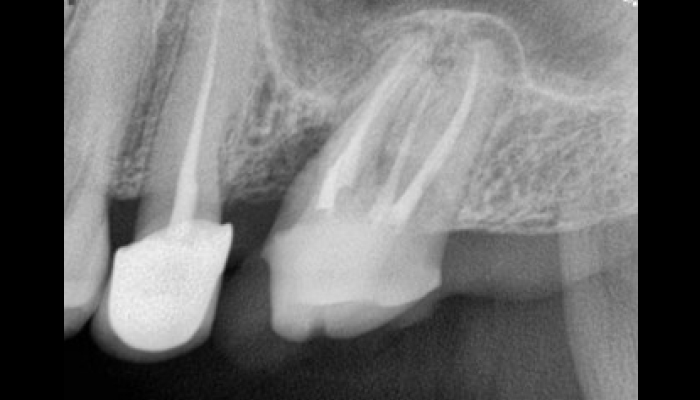

서울바른훈치과에서는 임상검사 및 바이트스트립, 필요시 치과에서 제작한 이갈이 검사장치를 이용하여 이갈이를 정확하게 진단하고 이와 동반된 치아시림, 턱관절장애, 안면부 근육통, 두통, 사각턱까지 총체적으로 치료가 가능합니다.